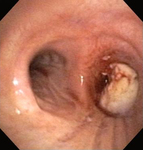

Bronchoscopic therapy for central airway obstruction of the right mainstem: post-mechanical debulking

From the collections of Jose Fernando Santacruz MD, FCCP, DAABIP and Erik Folch MD, MSc; used with permission